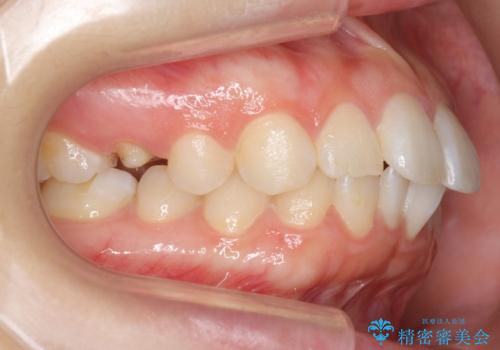

- 奥歯の詰め物のやり替えを希望して来院。

銀歯と、プラスチックをセラミックにかえました。

古い詰め物を取るときに、しっかり虫歯はとっています。

右上6番は詰め物が大きく、インレーではなくクラウンとしました。